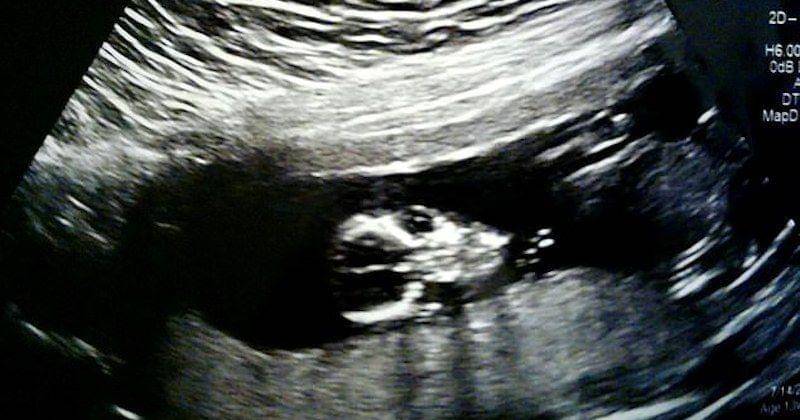

Penyakit langka OI memang membuat tulang penderitanya sangat mudah patah. Itu pula yang terjadi pada Theo, yang sudah mengalami patah tulang sejak ia masih dalam kandungan.

Di dalam perut, Theo sudah mengalami 6 tulang retak, tulang belikat kiri patah, dan dua tulang kaki patah. Sejak dilahirkan, kondisi justru semakin parah, karena hingga usianya 7 bulan ini Theo sudah mengalami 20 kali patah tulang.

Saat mengetahui janin di dalam perut Loni mengalami kondisi tulang yang sangat buruk, tim dokter menyarankan untuk melakukan aborsi saat hamil 20 minggu. Namun tanpa pikir panjang, Loni dan pasangannya, Craig, menolak saran tersebut.